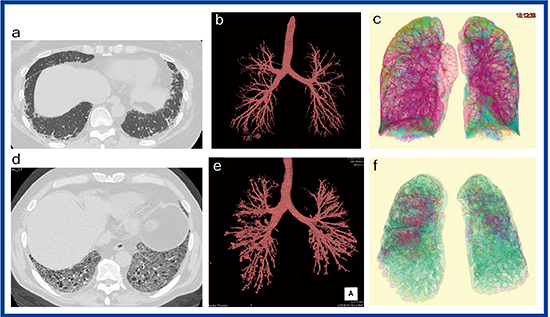

当センターの高精細CT「Aquilion Precision」(キヤノンメディカルシステムズ社製)の1024×1024・0.25mm厚の高精細画像では,従来の3D画像では描出が難しかった,末梢の気管支拡張についても3D画像で観察可能である(図1)。図1 bのようにリウマチ肺では比較的軽症の症例でも,末梢に囊胞状の気管支拡張が観察される。広範囲に間質性肺炎が広がる症例では,中枢側の気道にも気管支拡張が見られる(図1 e)。また,間質性肺炎が認められない症例で,気道病変が見られることもしばしばあり,リウマチ肺において気道病変を定量化することは病態把握に重要と考えられる。

図1に解析結果を示す。症例上(a〜c)は50歳代,女性,症例下(d〜f)は70歳代,男性で,いずれも関節リウマチと診断されている。気管支3D画像で見ると,症例上にも軽微な気管支拡張があり(図1 b),症例下では気管支拡張が高度であった(図1 e)。AWV% rlは,症例上が2.19%,症例下が5.22%であった。

図1 リウマチ肺のCT所見とその解析結果

症例上(a〜c) 50歳代,女性,病変のextent:19.2%,AWV% rl:2.19%

症例下(d〜f) 70歳代,男性,病変のextent:84.1%,AWV% rl:5.22%

a, d:1024×1024・0.25mm厚の高精細CT画像

b, e:高精細CTから作成した気管支3D画像 c, f:QZIP-ILDの解析結果(3D表示)